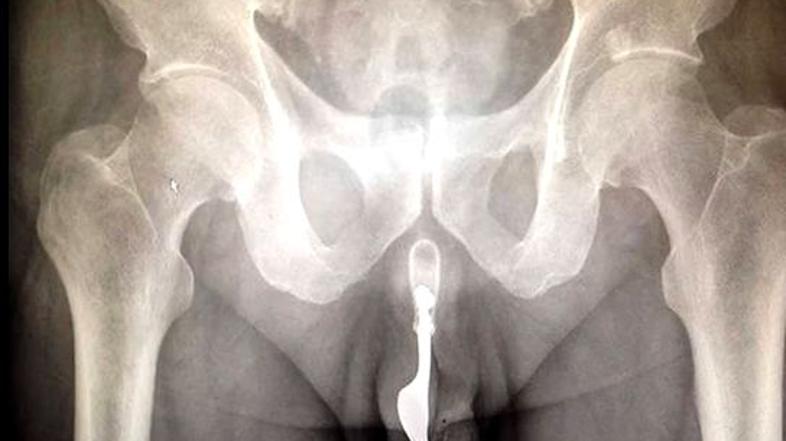

Neki 70-letni Avstralec je v svoj penis vstavil vilico in pristal v mednarodno priznani strokovni reviji o kirurgiji International Journal of Surgery.

Zdravniki v  Canberri so debelo pogledali, ko so na urgenco sprejeli 70-letnika, ki si je med samozadovoljevanjem v penis potisnil desetcentimetrsko vilico.

Možje v belem sprva niso vedeli, kaj je z moškim, ki je krvavel iz spolovila, narobe, saj vilice niso videli. Kot so zapisali v reviji, so se težavice lotevali na različne načine, na koncu pa so moškega rešili s pomočjo klešč in olja.